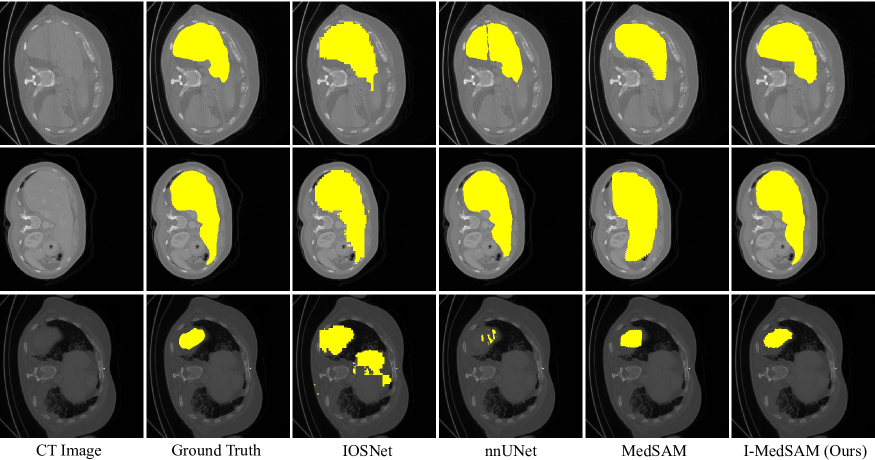

Refer to caption

Figure 5: Qualitative comparison on BCV dataset for liver segmentation. Best viewed in colors.

4.3 Qualitative Comparison

As shown in Fig. 4 and Fig. 5, we conduct the qualitative comparisons on datasets Kvasir-Sessile and BCV. Since SwIPE does not release code for inference, we remove it for visual comparison. We also provide input medical images and ground truth segmentation masks. From the figures, it can be witnessed that I-MedSAM obtains better segmentation boundaries. Thanks to the proposed frequency adapters and uncertainty guided sampling techniques, I-MedSAM can efficiently aggregate high-frequency information from the input, which is beneficial to the accuracy of final segmentation maps. Due to the space limitation, please refer to supplementary materials for more qualitative results.